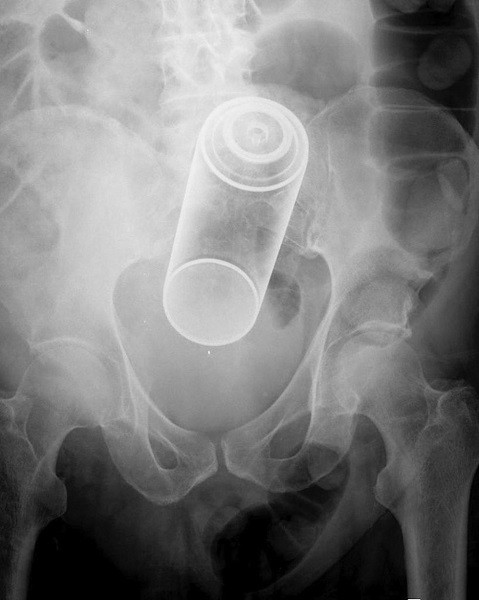

Avete presente le bombolette di gas che si usano per ricaricare gli accendini? Ecco, proprio quelle.

Contenitore di gas non meglio identificato. Vorrei avere una foto della faccia del radiologo quando l’ha esaminato.